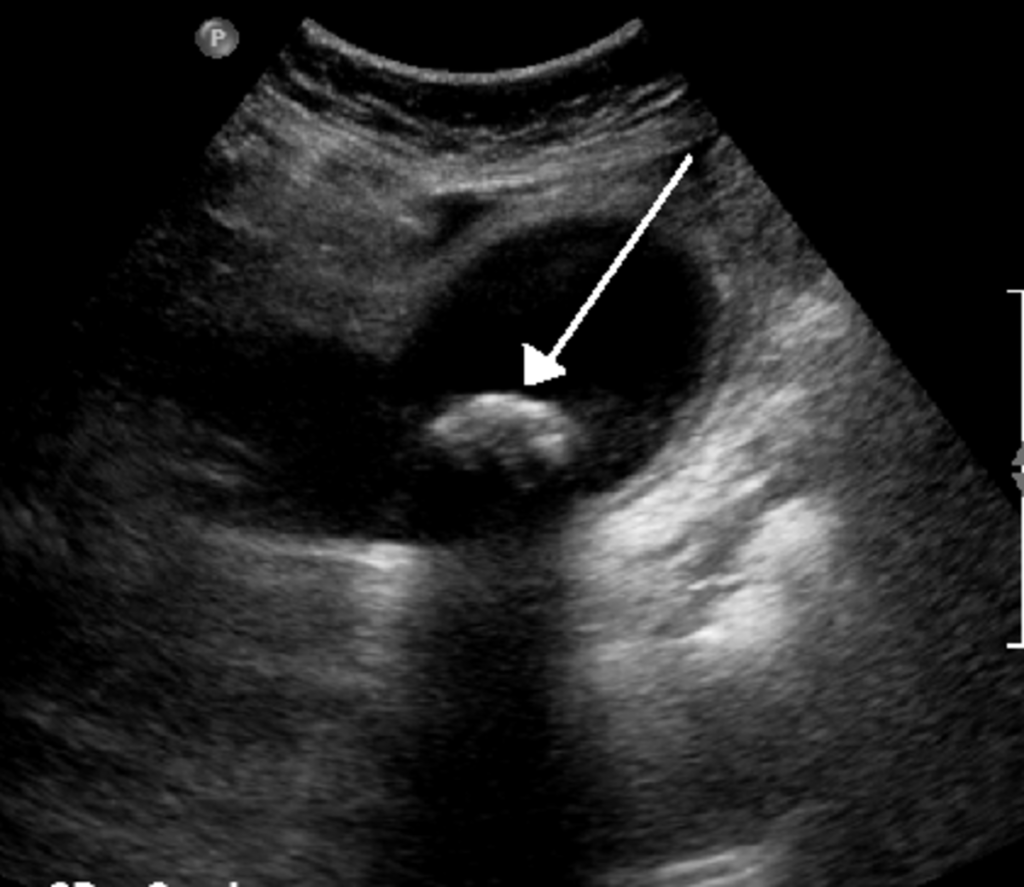

Ultrasound

- An ultrasound image is produced by recording ultrasonic sound waves that bounce off the tissues in the body.

- Ultrasound is particularly good at imaging certain organs, including the gall bladder and ovaries.

- Ultrasound is also very good for imaging a fetus because it does not use ionizing radiation.